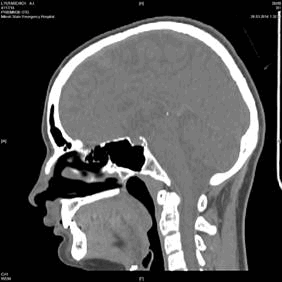

Краниологическое исследование пациентов проводилось в УЗ «Больница скорой медицинской помощи» г. Минска (Республика Беларусь) с помощью 16-срезового компьютерного томографа «General Electric LightSpeed Pro 16» и его программного обеспечения. В базе данных компьютерного томографа пациентов можно сортировать по возрасту, полу, области исследования, дате исследования и др. Сканирование пациентов осуществлялось в положении головы во франкфуртской горизонтальной (ухоглазничной) плоскости, которая проходит между наиболее низкой точкой глазницы и наиболее высокой точкой на верхнем крае наружного слухового прохода. Результат исследования выводится на экран в двухмерной сагиттальной и горизонтальной плоскостях (рис. 1 слева). Костные структуры выглядят светлыми, мягкие ткани — темными с разной степенью интенсивности цвета. Программное обеспечение томографа также позволяет произвести реконструкцию и построить трехмерное изображение черепа (рис. 1 справа).

Рис. 1. Режимы изображения в сагиттальной плоскости (двухмерный 2D — слева и трехмерный 3D — справа)